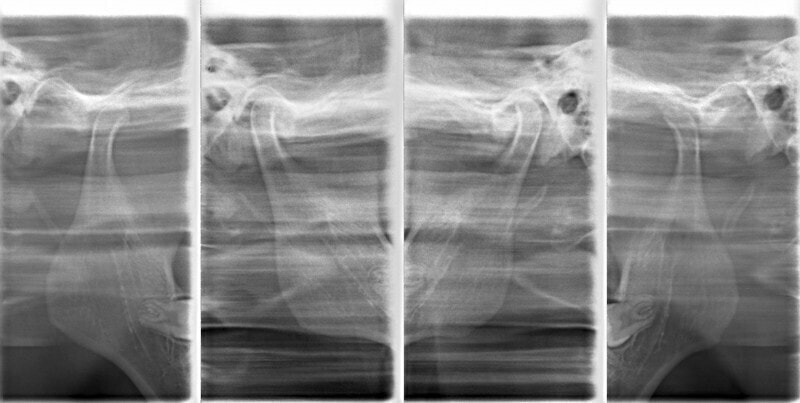

治療中のレントゲンです。

7番、8番の状態や歯根のパラレリング(平行性)をチェックしています。

左上2番の歯根の状態もなんとかもちそうです。

大臼歯は整直されております。

歯根のパラレリングは良好です。

左上2番の歯根も問題なさそうです。